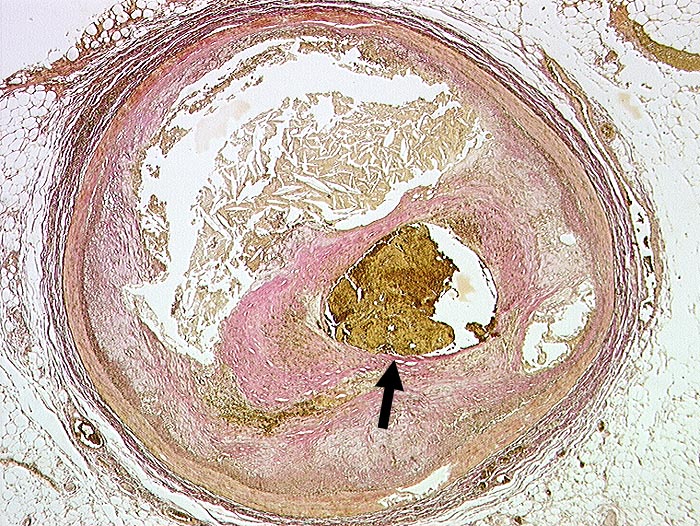

Koronarthrombose

Arteria coronaris

Exzentrische Stenose von mehr als 75% des Lumendurchmessers. Atherom mit herausgelösten Cholesterinkristallen. Intraluminale frische Thrombose.

Transmuraler akuter Myokardinfarkt mit Myokardruptur bei thrombotischem Verschluss des RIVA.

Diabetes mellitus Typ II und Adipositas.